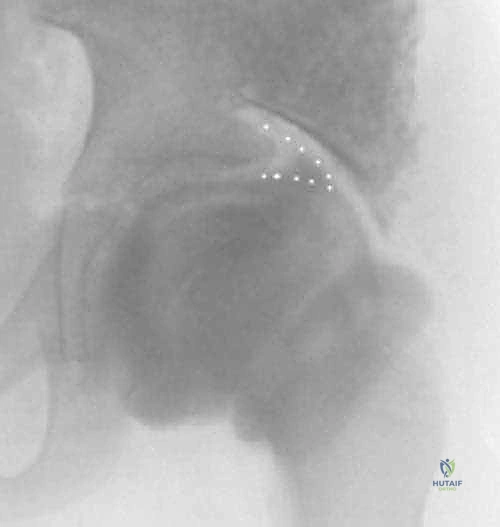

- الأشعة السينية (X-rays): صور شعاعية للكتفين والرقبة والعمود الفقري بأوضاع مختلفة لتقييم موقع لوح الكتف والبحث عن العظم الكتفي الفقري والتشوهات العظمية الأخرى.

- الأشعة المقطعية ثلاثية الأبعاد (3D CT Scan): تعتبر الأداة الأهم في التخطيط الجراحي. توفر صورة مجسمة دقيقة للتشريح العظمي، وتحدد بدقة متناهية حجم وموقع العظم الكتفي الفقري (Omovertebral bone) وعلاقته بالفقرات العنقية، مما يمنع المفاجآت أثناء الجراحة.